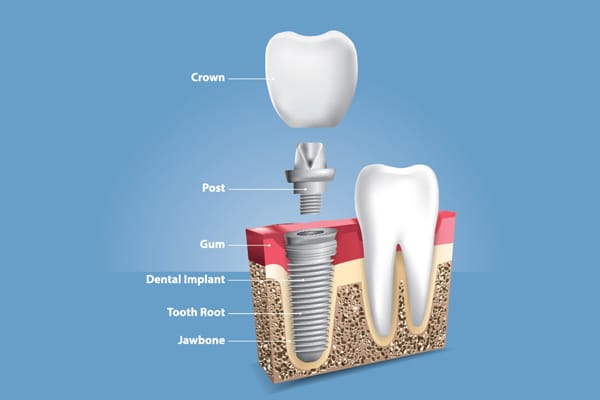

Dental implants and prosthodontic treatments focus on replacing missing teeth and restoring oral function, comfort and aesthetics. These

treatments help improve chewing ability, speech and overall confidence.

Dental implants are a well-established and safe treatment option when

planned and placed after proper evaluation by a dental professional.

Crowns and bridges are recommended to restore damaged or missing teeth,

improve strength and protect remaining tooth structure while maintaining

natural appearance.